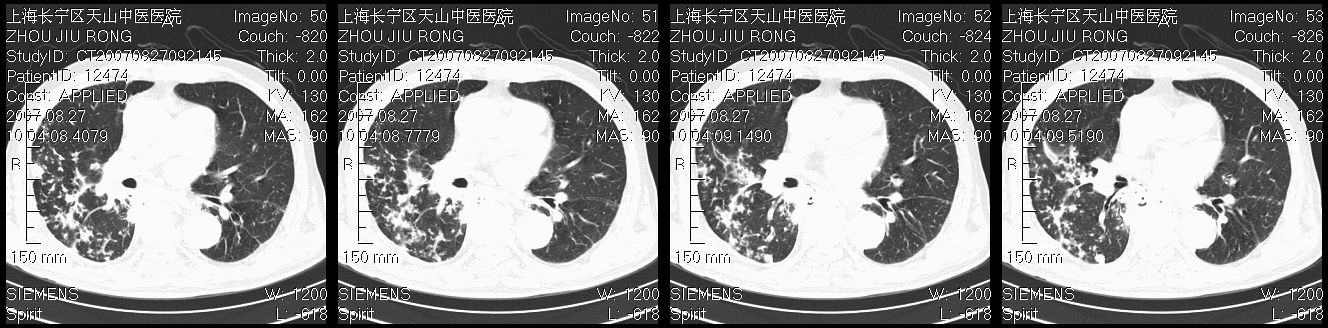

以下是引用zjzjr在2007-8-30 21:47:00的发言:[br]双肺弥漫性结节状、斑片状影,部分形成空洞,病灶以双肺上叶为著(符合结核发病部位),纵隔内见肿大淋巴结影。支持双肺继发性结核伴右上肺空洞形成。

以下是引用zjzjr在2007-8-30 21:47:00的发言:[br]双肺弥漫性结节状、斑片状影,部分形成空洞,病灶以双肺上叶为著(符合结核发病部位),纵隔内见肿大淋巴结影。支持双肺继发性结核伴右上肺空洞形成。

以下是引用gaoshengjiang在2007-8-31 10:24:00的发言:[br]双肺弥漫性斑片状影及多发空洞影,其间夹杂多量条索状影,胸膜肥厚、粘连并有结节状改变,纵隔多枚淋巴结肿大,考虑1双肺继发型肺结核合并感染?2韦格氏肉芽肿?[br] 支持!

以下是引用zjzjr在2007-8-30 21:47:00的发言:[br]双肺弥漫性结节状、斑片状影,部分形成空洞,病灶以双肺上叶为著(符合结核发病部位),纵隔内见肿大淋巴结影。支持双肺继发性结核伴右上肺空洞形成。

以下是引用zjzjr在2007-8-30 21:47:00的发言:[br]双肺弥漫性结节状、斑片状影,部分形成空洞,病灶以双肺上叶为著(符合结核发病部位),纵隔内见肿大淋巴结影。支持双肺继发性结核伴右上肺空洞形成。

以下是引用zjzjr在2007-8-30 21:47:00的发言:[br]双肺弥漫性结节状、斑片状影,部分形成空洞,病灶以双肺上叶为著(符合结核发病部位),纵隔内见肿大淋巴结影。支持双肺继发性结核伴右上肺空洞形成。